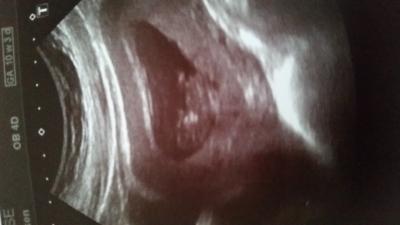

Hi Hatte heute meinen Frauenarzttermin nachdem ich letzte Woche 8 Tage zurückdatiert wurde ist jetzt wieder alles normal juhuuu. Endlich habe ich Hoffnung und Freude .Mein Krümel ist jetzt 10+2 ca 3,6 cm und somit zeitgerecht . Puhh liebe grüße

Bild zu Frauenarzttermin heute :-) - Forum für März - Mamis